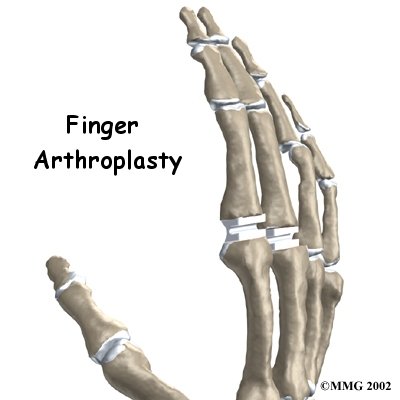

The finger joints work like hinges when they bend and straighten. The main knuckle joint is the metacarpophalangeal joint (MCP joint). It is formed by the connection of the metacarpal bone in the palm of the hand to the finger bone, or phalange. Each finger (the thumb is not termed a finger) has three phalanges, separated by two interphalangeal joints (IP joints). The one closest to the MCP joint (knuckle) is called the proximal IP joint (PIP joint). The joint near the end of the finger is called the distal IP joint (DIP joint).

Surgeons use silicon plastic implants to replace the original joint surfaces. The artificial joint functions the same way a hinge on a door does.